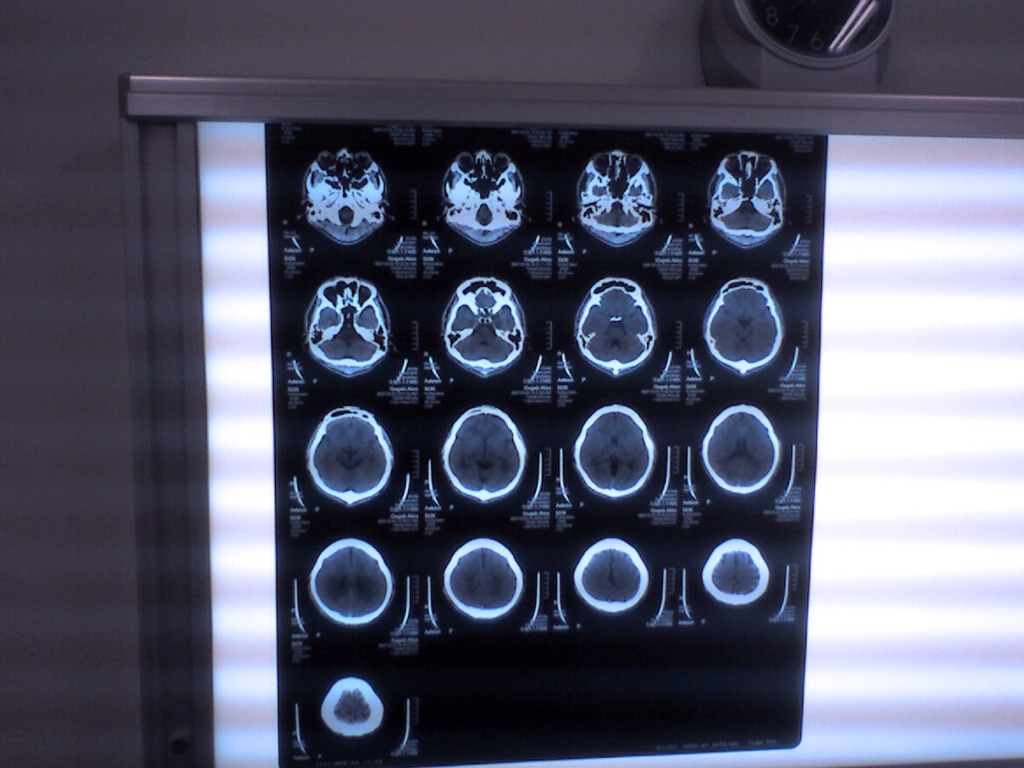

Computed Tomography (CT)

Although also based on the variable absorption of x rays by different tissues, computed tomography (CT) imaging, also known as "CAT scanning" (Computerized Axial Tomography), provides a different form of imaging known as cross-sectional imaging. The origin of the word "tomography" is from the Greek word "tomos" meaning "slice" or "section" and "graphe" meaning "drawing." A CT imaging system produces cross-sectional images or "slices" of anatomy, like the slices in a loaf of bread. The cross-sectional images are used for a variety of diagnostic and therapeutic purposes.

The data are sent to a computer to reconstruct all of the individual "snapshots" into a cross-sectional image (slice) of the internal organs and tissues for each complete rotation of the source of x rays.

CRANIAL CT SCAN